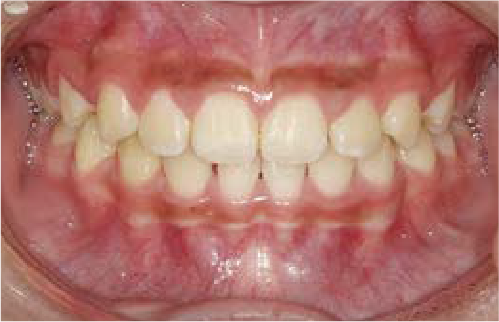

Jさん (矯正開始時:8歳)

Before

After

歯がガタガタに並んでいて、前歯の真ん中の位置が少し左にずれていました。

奥歯が生えるためのスペースが足りず、永久歯が生えて来られない状況が確認できました。

また、飲み込むとき下くちびるに力が入ってしまうクセが見られ、お顔全体の成長が遅れている様子が確認できました。

治療を終えて

歯がきれいに生えるためのスペースをしっかり確保することができ、歯並びを乱していたお口のクセも改善されたため、奥歯が生えるスペースを確保することができました。

しっかり噛めるかみ合わせを作ることが、将来の健康につながるので「よく噛む」練習も続けてもらっています。

主訴・治療内容 歯がガタガタになってきたことに悩み、無料相談に来院されました。

治療期間 3年

費用 462,000円(税込)